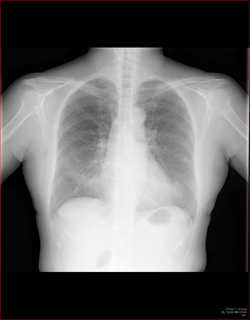

縦隔の所見

縦隔を見るときに、ボーッと見ていては所見を見逃します。

各種の線を追いかけていきましょう。

こちらを見て下さい。